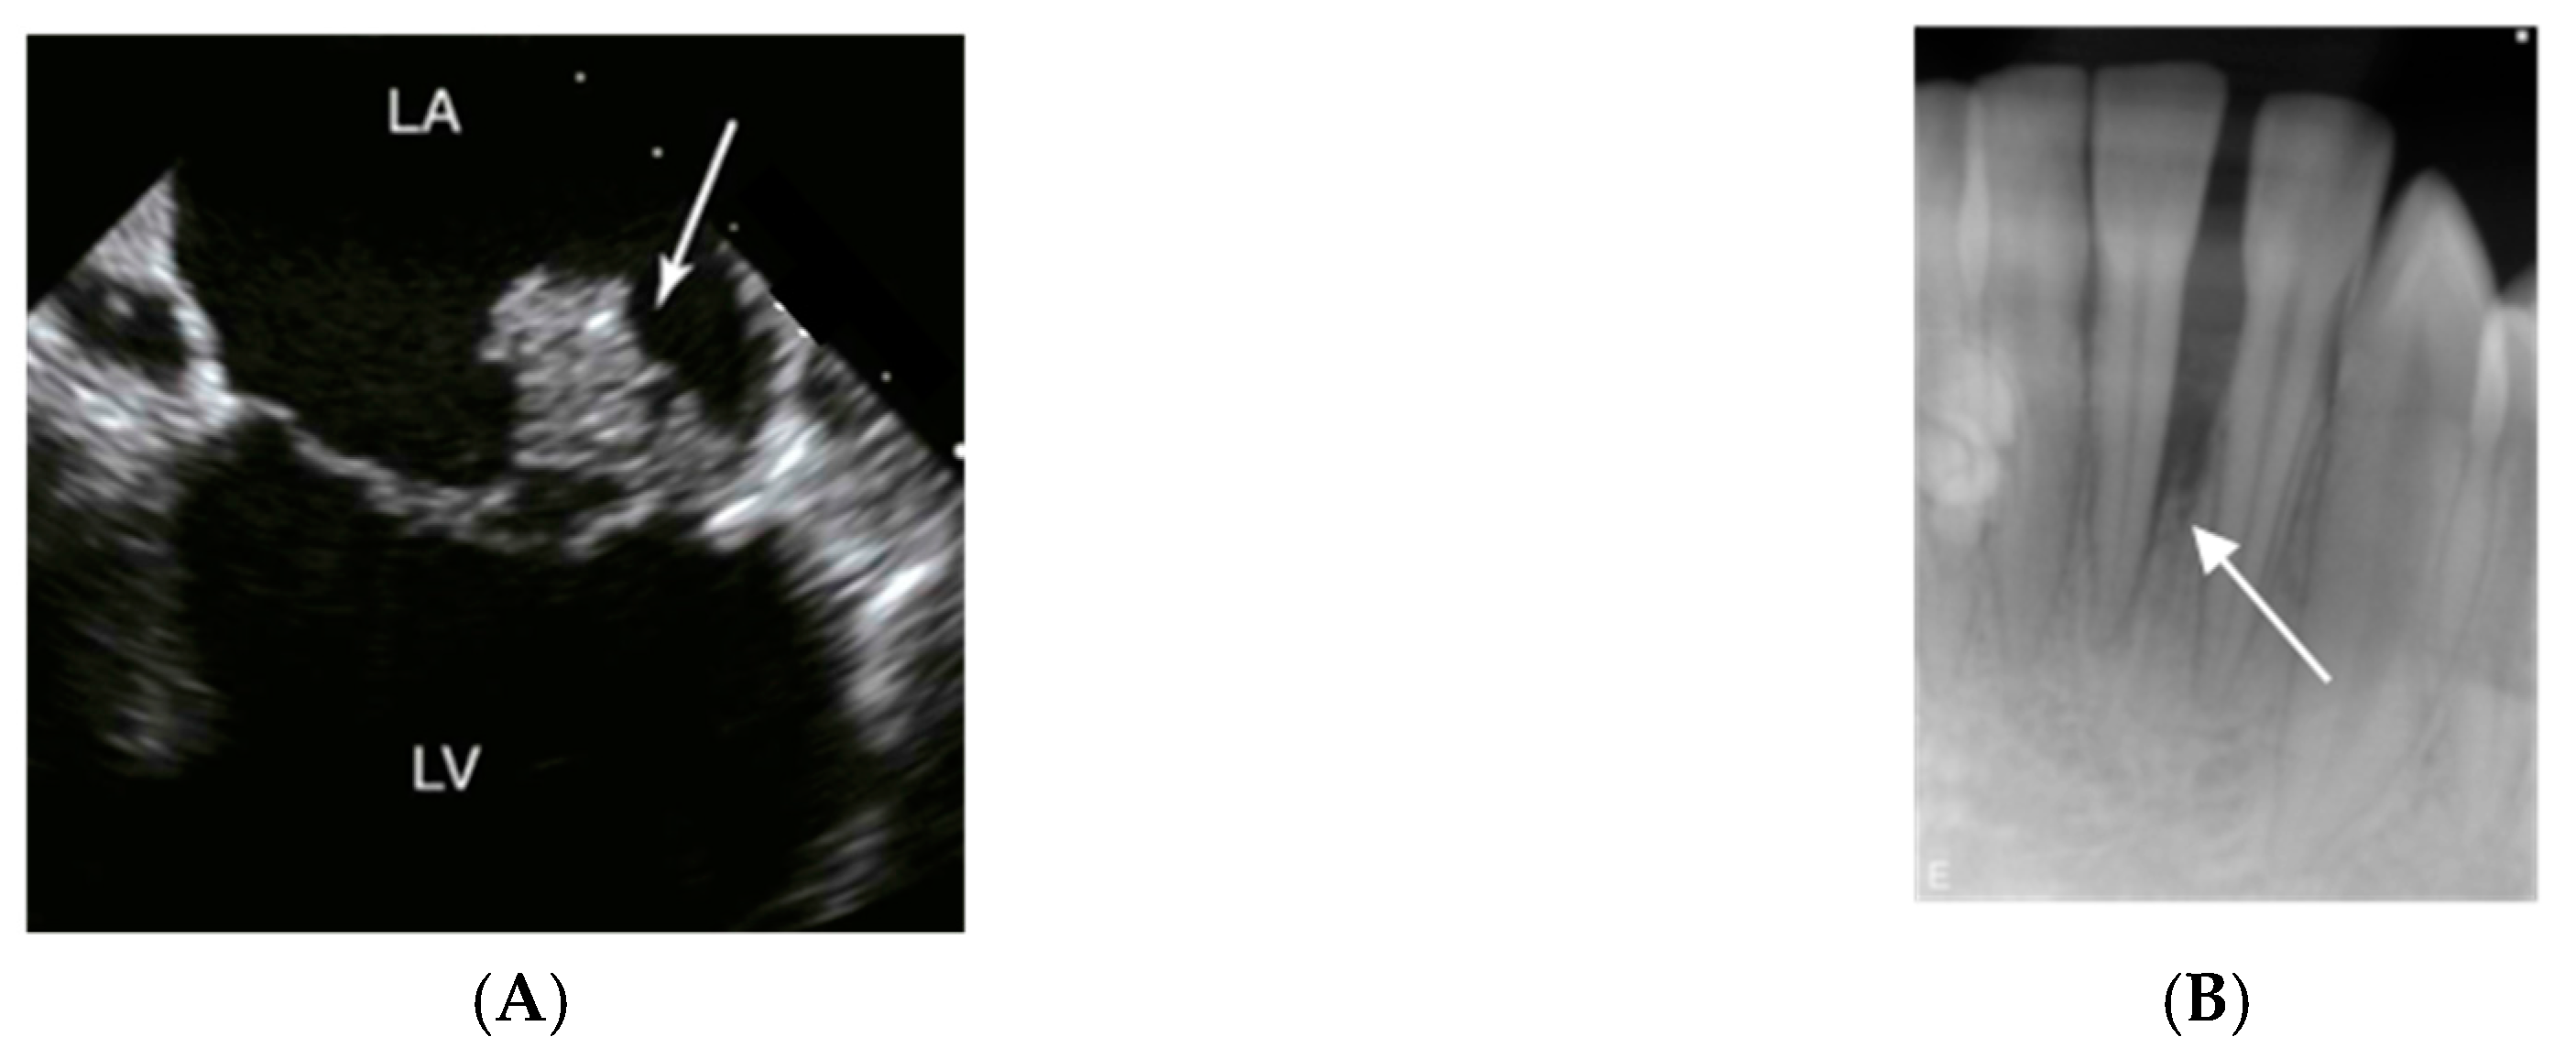

Infective endocarditis is an infection of the endocardium, the lining of the interior surfaces of the chambers of the heart. It usually affects the heart valves (Figure 3A), where corrosion and incidental exposure of sub-endothelium tissue during the extensive motion of the valves may serve as a starting point for bacterial adhesion.

Figure 3.

Imaging signs of infections and inflammation that may be associated with A. actinomycetemcomitans. (A) Transesophageal echocardiography of a heart with mitral valve infective endocarditis. The arrow marks a large vegetation on the posterior leaflet between left atrium (LA) and left ventricle (LV); usually, vegetations caused by A. actinomycetemcomitans are of smaller size. (B) 14-year old girl of African ethnicity. The radiograph shows an extensive and apparently rapid loss of the periodontal support of the lower incisor 31. Pictures by courtesy of close clinical collaborators of the authors.

Periodontitis is an inflammatory disease associated with loss of connective tissue and bone around teeth (Figure 3B). The bacterial tooth biofilm initiates the gingival inflammation, and further progression of the periodontal lesion depends on dysbiotic ecological changes within the gingival sulcus area. Unfavourable lifestyles and hygiene contribute to the development and progression of periodontitis, which has been designated as one of mankind’s most common chronic inflammatory diseases [48].